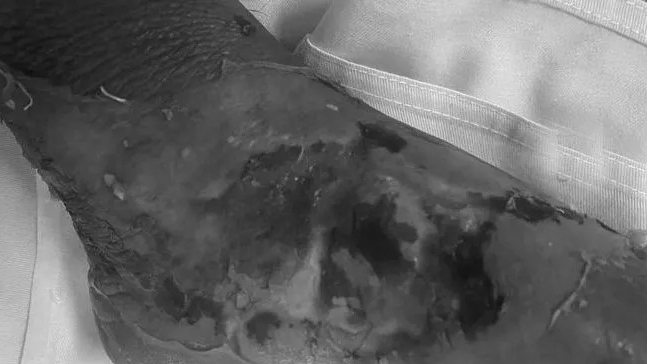

Bệnh nhi được người nhà đưa đến Bệnh viện Đa khoa Hùng Vương (Phú Thọ) trong tình trạng quấy khóc, vùng bỏng 2 bàn chân sưng nề chảy dịch đục, trợt da, từ cổ chân đến các ngón chân da bẩn, nhựa lá cây dính bết vào vết bỏng, hai bàn chân nhiễm trùng nặng, cử động cổ chân hạn chế.

Người nhà bệnh nhi cho biết, bé vô tình cho cả hai chân vào chậu nước sôi vừa rót ra chậu. Ở nhà, bé được điều trị bằng đắp thuốc nam nhưng sau đó bé quấy khóc, sốt, vết bỏng chảy dịch đục, bé không ăn, bàn chân sưng nề nên gia đình đưa bé đến bệnh viện khám.

Bác sĩ xác định: Bệnh nhi bị bỏng ở mức độ II, III nếu sau khi bị bỏng đến bệnh viện xử lý vết thương ngay thì thời gian phục hồi sẽ nhanh chóng, tránh các biến chứng nguy hiểm. Nhưng do không được điều trị đúng cách, bệnh nhi hiện tại bị nhiễm trùng nặng hai bàn chân, nguy cơ nhiễm trùng huyết và có thể nguy hiểm đến tính mạng bất cứ lúc nào.